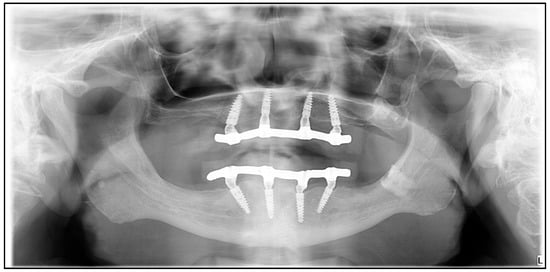

2.1. Study Design, Patient Treatment Characteristics

2.3. Modeling